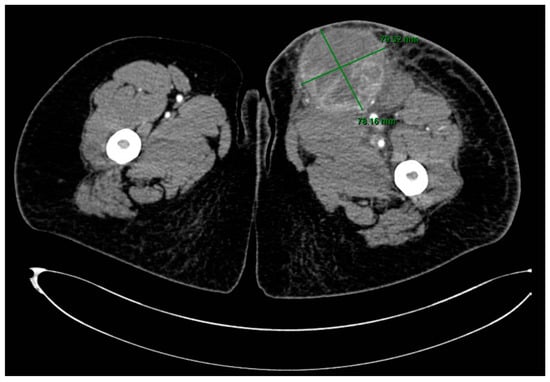

A CT scan of the thigh in an emergency setting showed a well-delineated, large mass of 8.6/7.7 cm, with extensive areas of necrosis, exhibiting intense and heterogeneous contrast enhancement, situated in contact posteriorly with the muscular planes, with densification of the perilesional subcutaneous cellular tissue and capturing inguinal lymphadenopathy up to 21.4 mm in diameter (Figure 2).

Figure 2. CT scan of the lower left limb showing a large mass in the upper thigh.